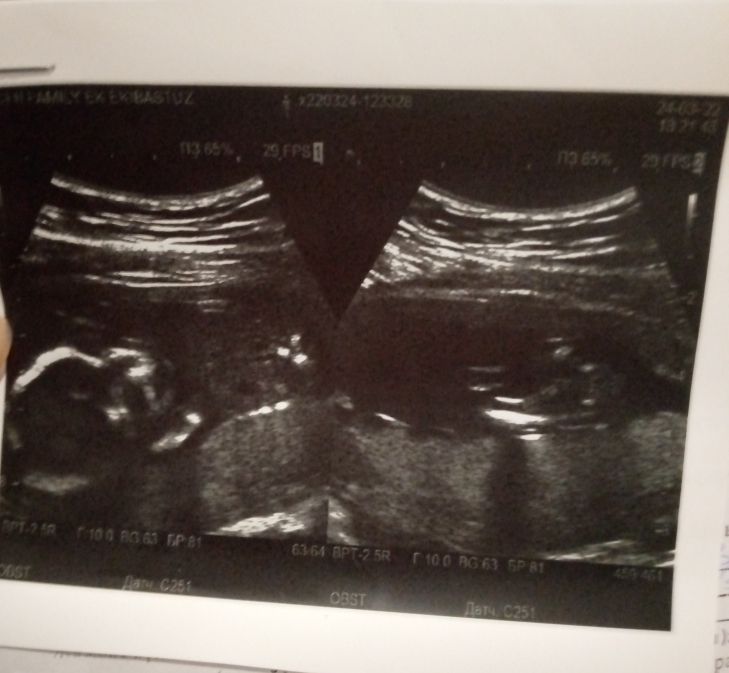

Девочки кто хорошо разбирается в снимках УЗИ, объясните мне где что у малышки

Прошла УЗИ 17 недель, и вот что то снимок забрала а не спросила что на снимках, на первом понятно сам малыш а вот что на втором не могу понять, может кто подскажет как малышка лежит?